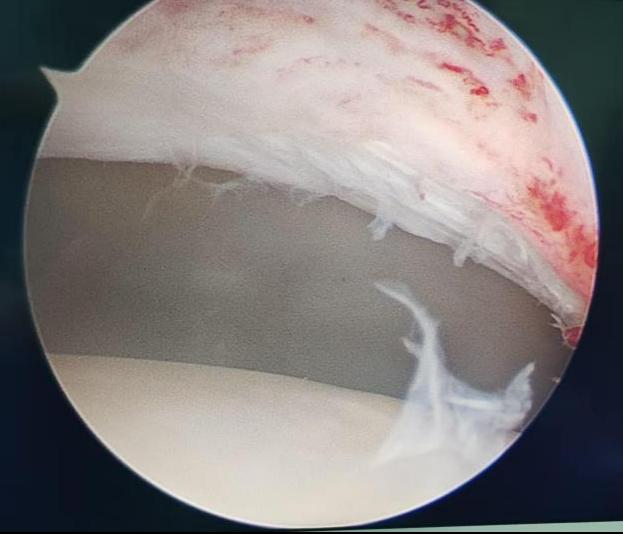

该病常伴随盂唇损伤,长期拖延会加重疼痛、加速关节退变。经充分评估与沟通,关节运动医学团队为王女士制定了微创、精准、快速康复的手术方案:关节镜下髋关节撞击股骨颈成形 + 盂唇修复术。经过术前检查,无手术禁忌,手术顺利开展,全程用时不到 1 小时。

1.小切口、大视野、精修复

2.仅在髋部做数个几毫米 “钥匙孔” 切口

3.不切断肌肉、不广泛剥离组织

4.镜下清晰视野,精准打磨增生骨质

5.完美修复损伤盂唇,重建髋关节正常结构